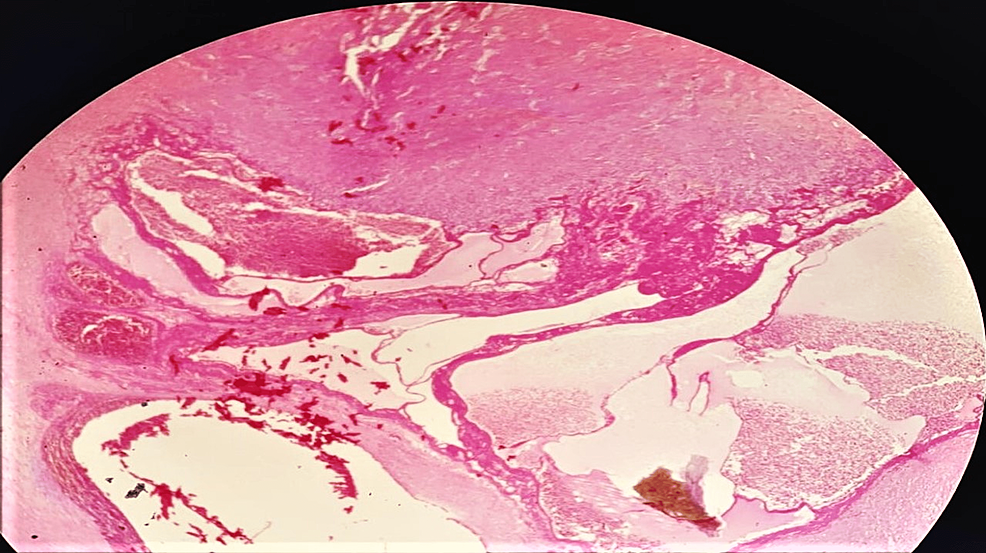

Morel Lavallee Lesion Histology. It most commonly occurs in the thigh, hip, and pelvis.

It most commonly occurs in the thigh, hip, and pelvis.